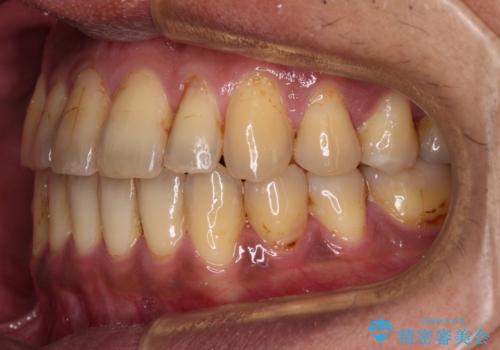

前歯のクロスバイトを改善 ワイヤー装置での非抜歯矯正

- 骨格的な咬み合わせのズレ、前歯のデコボコとクロスバイトを気にして来院された患者様です。

骨格のズレが顕著であると診断され、マウスピース矯正では奥歯の咬み合わせが整えにくいと判断し、ワイヤー装置による矯正治療を行うこととしました。

上下の叢生は速やかに改善できましたが、右側のクロスバイトの改善に1年以上の期間を要しました。